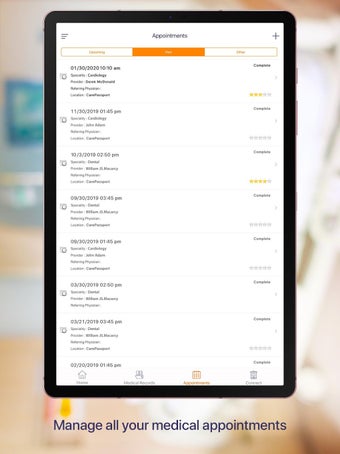

Carepassport là một ứng dụng Android cung cấp cho bệnh nhân một giải pháp toàn diện để quản lý dữ liệu y tế của họ. Ứng dụng cho phép bệnh nhân truy cập và lưu trữ an toàn dữ liệu y tế của mình, lên lịch hẹn, xem hình ảnh y tế, báo cáo xét nghiệm và lâm sàng từ các nhà cung cấp khác nhau, và chia sẻ chúng bằng công nghệ tính toán di động tiên tiến. Với Carepassport, bệnh nhân có thể dễ dàng quản lý nhu cầu chăm sóc sức khỏe của mình chỉ với vài lần chạm trên thiết bị di động của họ.

Một trong những tính năng quan trọng nhất của ứng dụng là việc truy cập dữ liệu y tế một chạm dễ dàng. Bệnh nhân có thể truy cập dữ liệu y tế của mình hoặc dữ liệu đại diện gia đình một cách an toàn và nhanh chóng, làm cho nó trở thành một công cụ tuyệt vời để quản lý lịch sử bệnh án của họ. Ứng dụng cũng cho phép người dùng tìm kiếm các phòng khám và bệnh viện gần đó, lên lịch hẹn, và thậm chí nhận chỉ đường đến cuộc hẹn của họ qua Uber. Ngoài ra, bệnh nhân có thể giao tiếp với nhà cung cấp chăm sóc của họ qua tin nhắn an toàn, chia sẻ hình ảnh y tế và cho phép thành viên gia đình truy cập dữ liệu y tế của họ thông qua cài đặt proxy an toàn. Cuối cùng, ứng dụng cung cấp tài liệu giáo dục liên quan đến chăm sóc sức khỏe và có thể kết nối với các thiết bị đeo được hoặc nhập dữ liệu y tế thủ công.